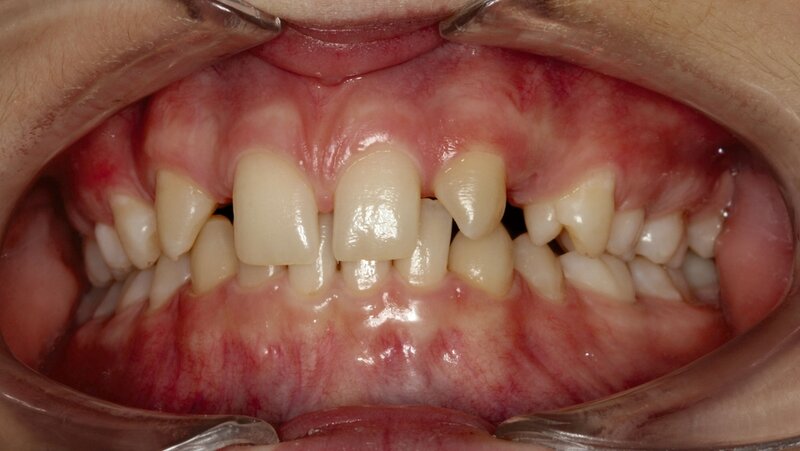

Bei dem gut zwölfjährigen Mädchen sind die seitlichen oberen Schneidezähne (Zähne 12 und 22) nicht angelegt. Zusätzlich zeigten sich verlagerte zweite obere Prämolaren.